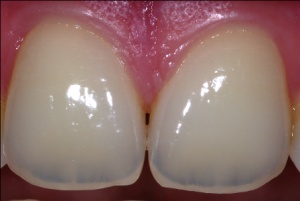

„Combat readiness“ heißt auch „dental readiness“. Nach Liewehr [8] stellen sich innerhalb eines Jahres um die 20 – 25 % der Soldatinnen und Soldaten im Einsatz mit Zahnproblemen vor, was sich für eine US-Division auf 18 720 Mann-Tage zahnmedizinischer Notfälle aufsummieren kann. Nicht umsonst wird deshalb vor dem Einsatz versucht, die laut NATO Standardisation Agreement (STANAG) 2466 erforderlichen Dental-Fitness-Klassen 1 und 2 zu erreichen. Das ist aber leider auch nicht immer möglich, insbesondere wenn es Personal ist, das für eine spezielle Verwendung ausgebildet sind. So sind für den Sanitätsstabsoffizier (SanStOffz) Zahnarzt aus aktueller wie aus strategischer Sicht Entscheidungen zu fällen, die unter zivilen, alltäglichen Bedingungen gegebenenfalls anders ausfielen. Hier ist es besonders wichtig, dass bei Reduzierung des Zahnbestandes darauf zu achten ist, dass eine wenn möglich festsitzende prothetische Versorgung erreicht wird, also auch die Einschätzung von Zähnen unter dem Aspekt der prothetischen Wertigkeit erfolgt (Abb. 1).

- Foto 1: Lampe, Bless, Wetzel, Lehmann: Parodontale Sanierung aggressiver Parodontitis. Dental-Praxis 6, 1998, Titelbild.